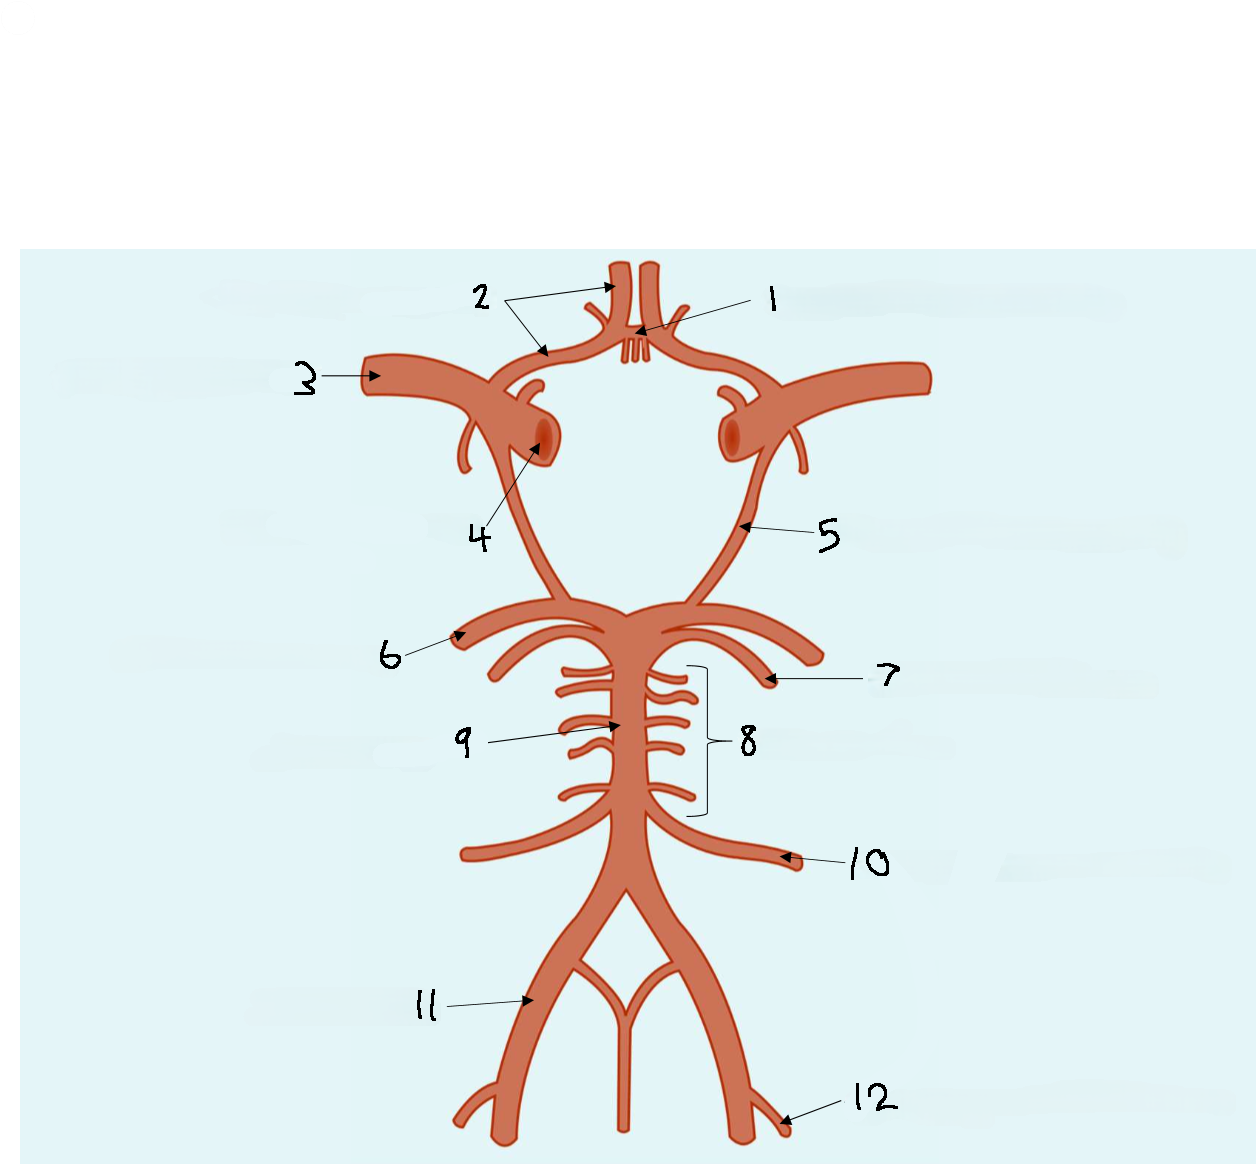

What is 1?

anterior communicating artery

What is 2?

anterior cerebral artery

What is 3?

middle cerebral artery

What is 4?

internal carotid artery

What is 5?

posterior communicating artery

What is 6?

posterior cerebral artery

What is 7?

superior cerebellar artery

What is 8?

pontine arteries

What is 9?

basilar artery

What is 10?

anterior inferior cerebellar artery

What is 11?

vertebral artery

What is 12?

posterior inferior cerebellar artery